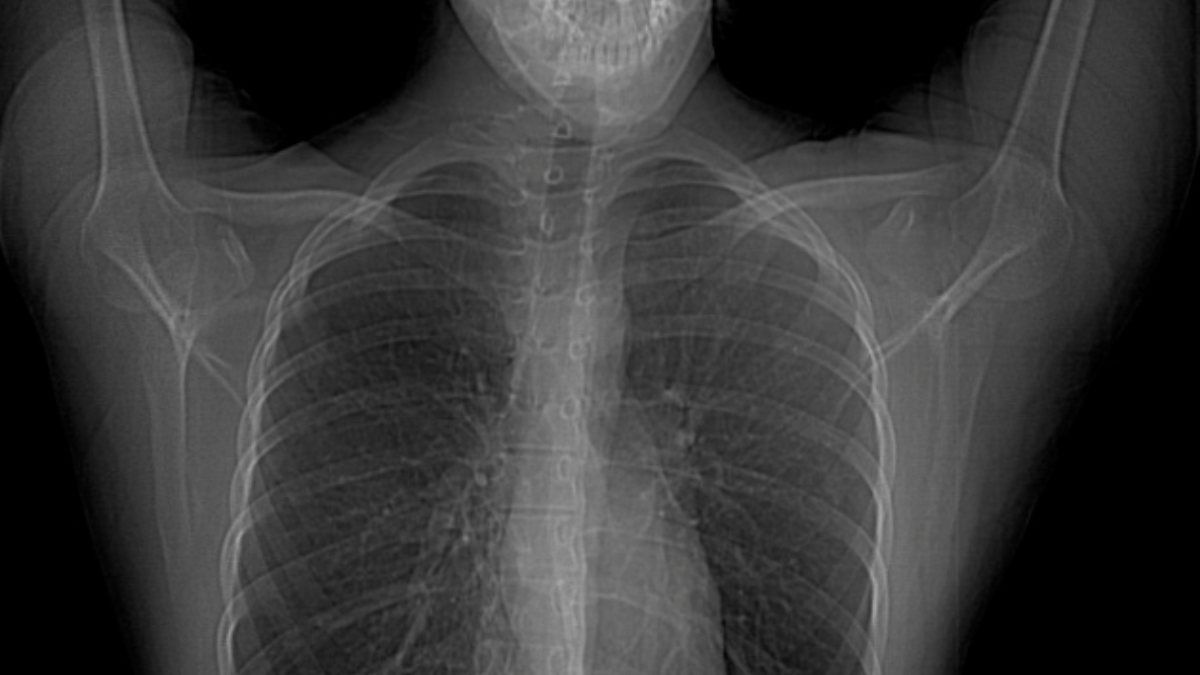

Hastanın vücut yapısı simetrik değildir. Yani vücudun bir yarısıyla diğer yarısı arasında görüntü ve yapı farklılıkları vardır. Özellikle göğüs bölgesinde bulunan yapılarda anormallikler bulunmaktadır. Kişide meme ve meme başı yokluğu da beraberinde görülebilmektedir.

Hastaların göğüs kası olmadığı için bakıldığında simetrik bir görünüm bulunmamaktadır. Estetik bir görüntü olmaması nedeniyle fark edilirler.

Göğüste içbükey bir görünüm vardır. Yine aynı tarafta meme ve meme ucu yokluğu da beraberinde olabilmektedir. Göğüs kaslarına ek olarak kişinin sırt ve kaburgalarında bulunan kasların yokluğu veya burada bulunan kasların liflerinde eksiklik olabilmektedir.

En sık görülen formu meme başının küçük olması ve diğer meme başına oranla daha yukarı seviyede olmasıdır. Bazı hastalarda göğüs duvarında zıt hareket oluşumuna neden olabilecek hasarlı bir göğüs duvarı vardır.

Yani normalde nefes alırken göğüs duvarı genişler ve böylelikle akciğere rahatlıkla hava dolar. Ama burada göğüs duvarı kısıtlama yaptığı için akciğer yeterince genişleyip hava alamaz. Hastada nefes darlığı gibi akciğerle ilgili sıkıntılar görülebilmektedir.